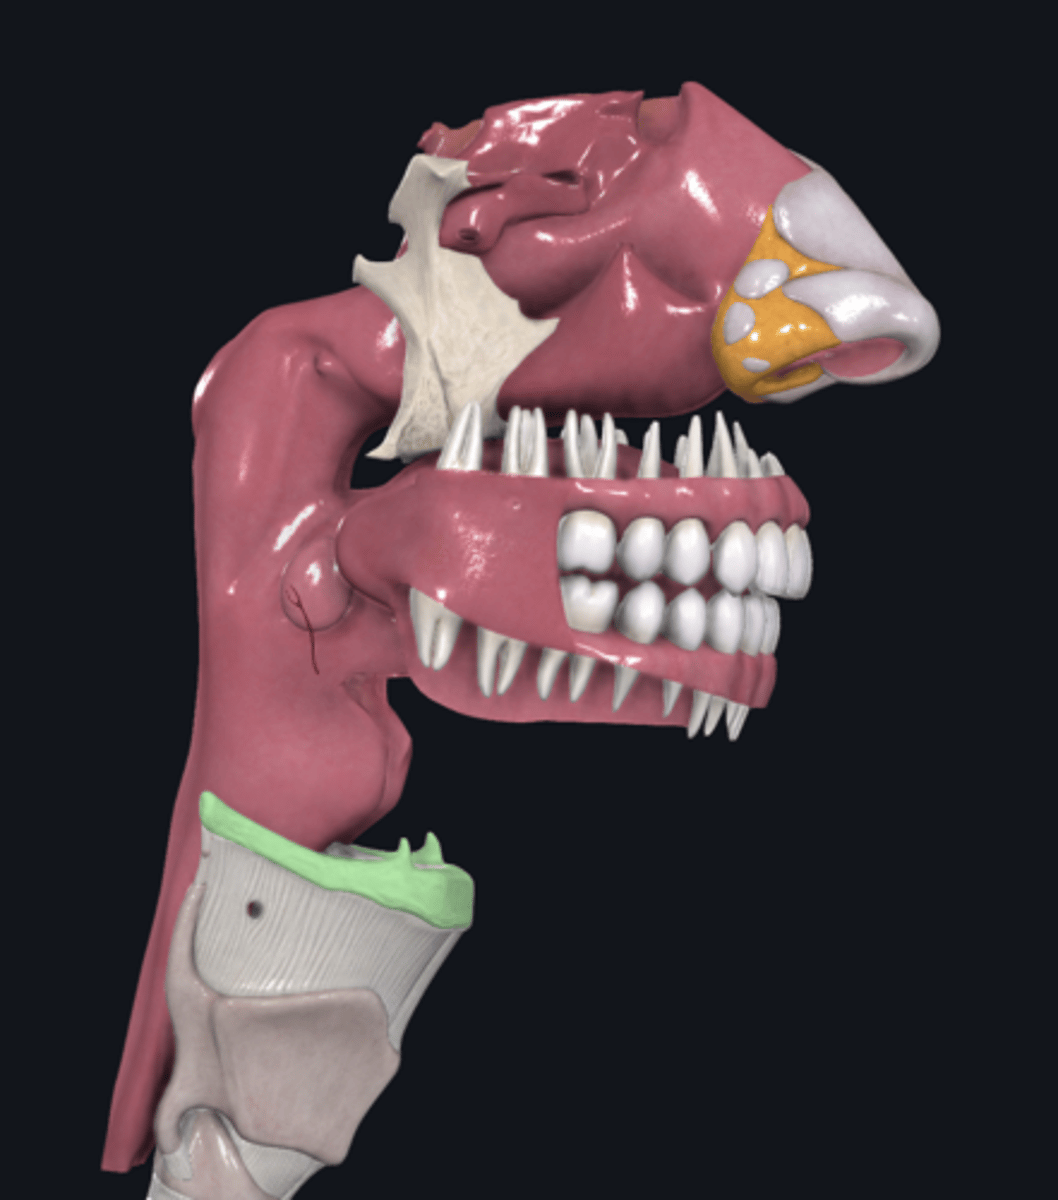

larynx

name the green portion

thyroid cartilage

name the green portion

cricoid cartilage

name the green portion

arytenoid cartilage

name this cartilage

vocal ligament

name the ligament in this area

vocalis muscle

name this muscle

trachea

tracheal cartilages

annular ligament